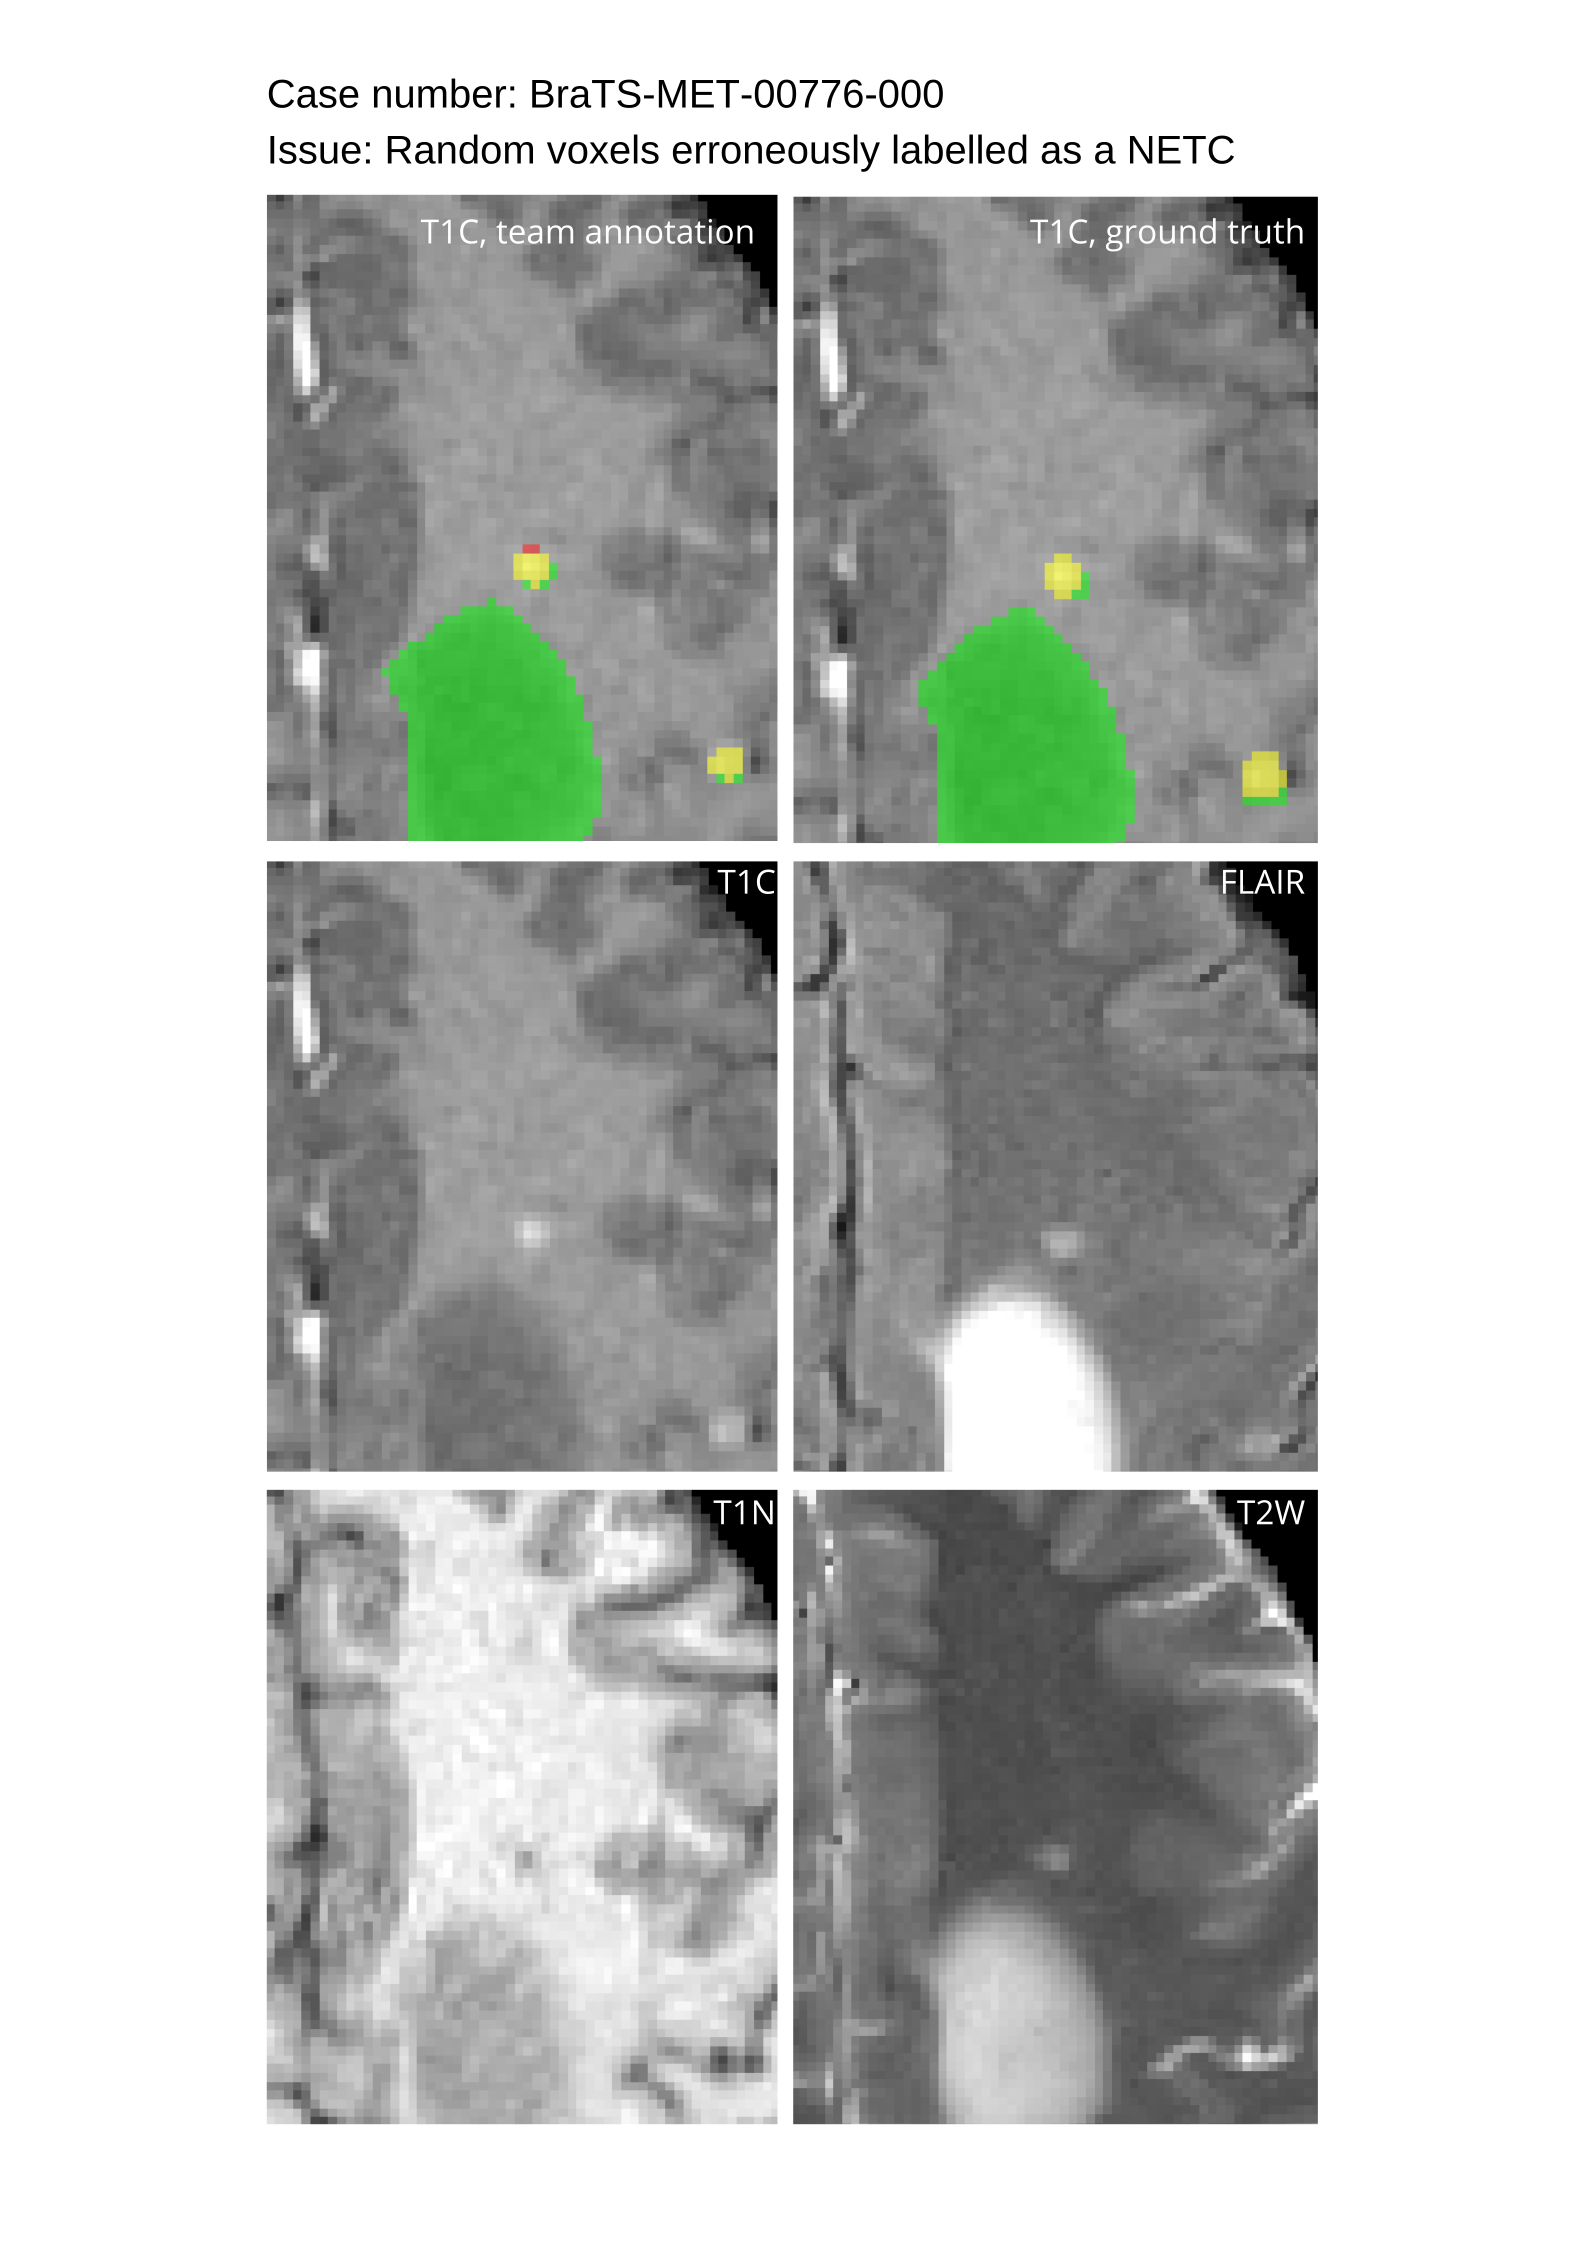

Approvers reviewed the volunteer annotations and either approved the case or returned it to students for re-annotation. Additionally, a QC process was implemented, which included removing all random voxels and any voxels outside the brain mask, ensuring all images had the same parameters (space, orientation, and origin) as the SRI24 atlas, and verifying the presence of all segmentations and segmentation masks are in the folder with original NIfTI images.